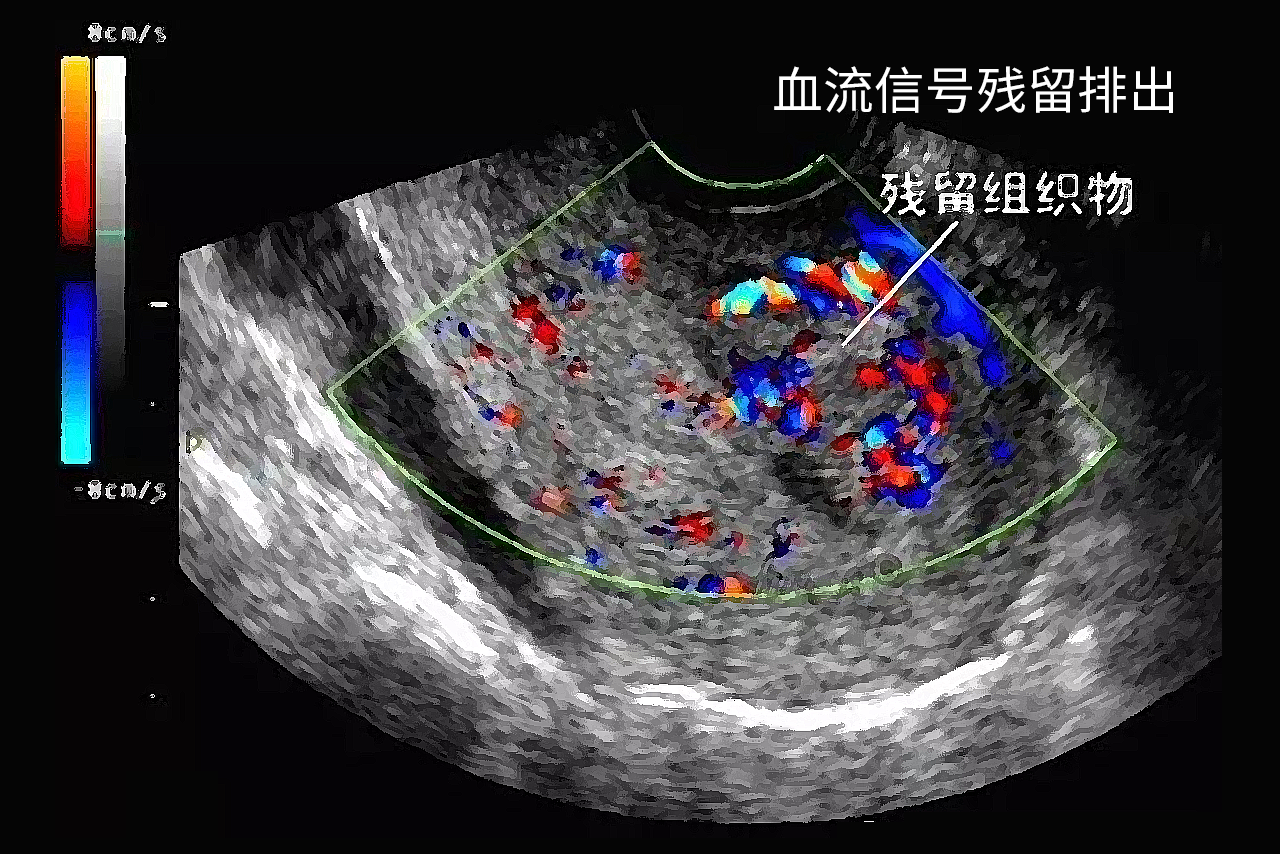

血流信号残留排出是指残留在宫腔的组织物多为胎盘、胎膜以及蜕膜等。血流信号一般是B超作出的提示,如果局部提示有血流信号,说明组织物具有生物活性的,如果强行手术,可能会导致出血增多。

子宫内残留高回声点状血流信号,有可能是子宫腺肌症、子宫内膜息肉,或流产后宫腔内有残留等因素引起。对于子宫腺肌症,是指子宫内膜间质和腺体长入子宫肌层内,临床表现为痛经和经量增多,B超时可见子宫内高回声点状血流信号。对于子宫内膜息肉,是指子宫内膜息肉是子宫内膜组织增生形成的条状组织物,临床表现为异常子宫出血,B超常常表现为子宫宫腔内的条状回声信号,首选宫腔镜检查加刮宫,排除子宫内膜癌和子宫黏膜下肌瘤。对于流产后宫腔内有残留妊娠物,流产不干净时,阴道仍有流血,B超检查提示宫腔内残留高回声血流信号。

对于血流信号比较小,残留比较低,在1公分以下,可以遵医嘱口服药物,例如活血化瘀的药物新生化颗粒、米非司酮、益母草合剂、血府逐瘀胶囊等。对于血流信号比较大,残留大于1公分,残留比较多,建议进行清宫。